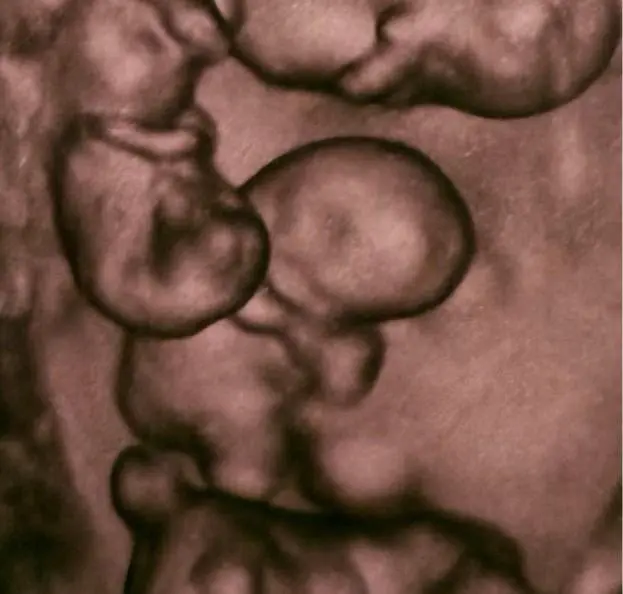

Монохориальная беременность — это разновидность однояйцевой, при которой все эмбрионы используют одну плаценту. Из-за общей системы кровоснабжения такая беременность сопряжена с высокими рисками и требует регулярного ультразвукового контроля с интервалом в 1-2 недели.

Также специалисты различают биамниотическую беременность (когда каждый плод находится в собственном амниотическом мешке) и моноамниотическую (когда эмбрионы развиваются в общей амниотической полости).